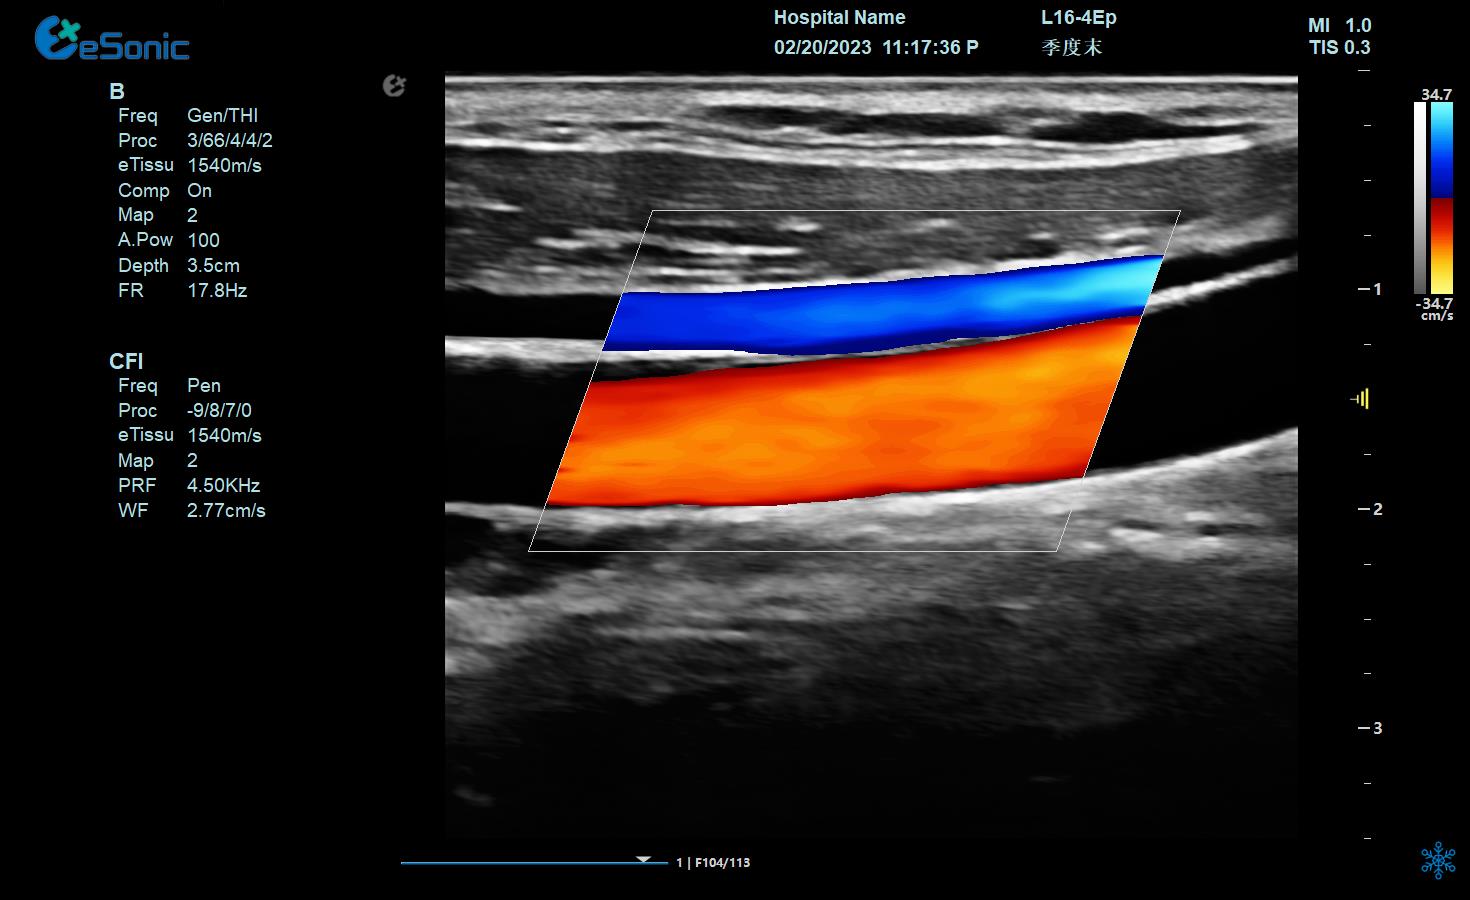

e 智IMT

颈部血管

桡浅动脉